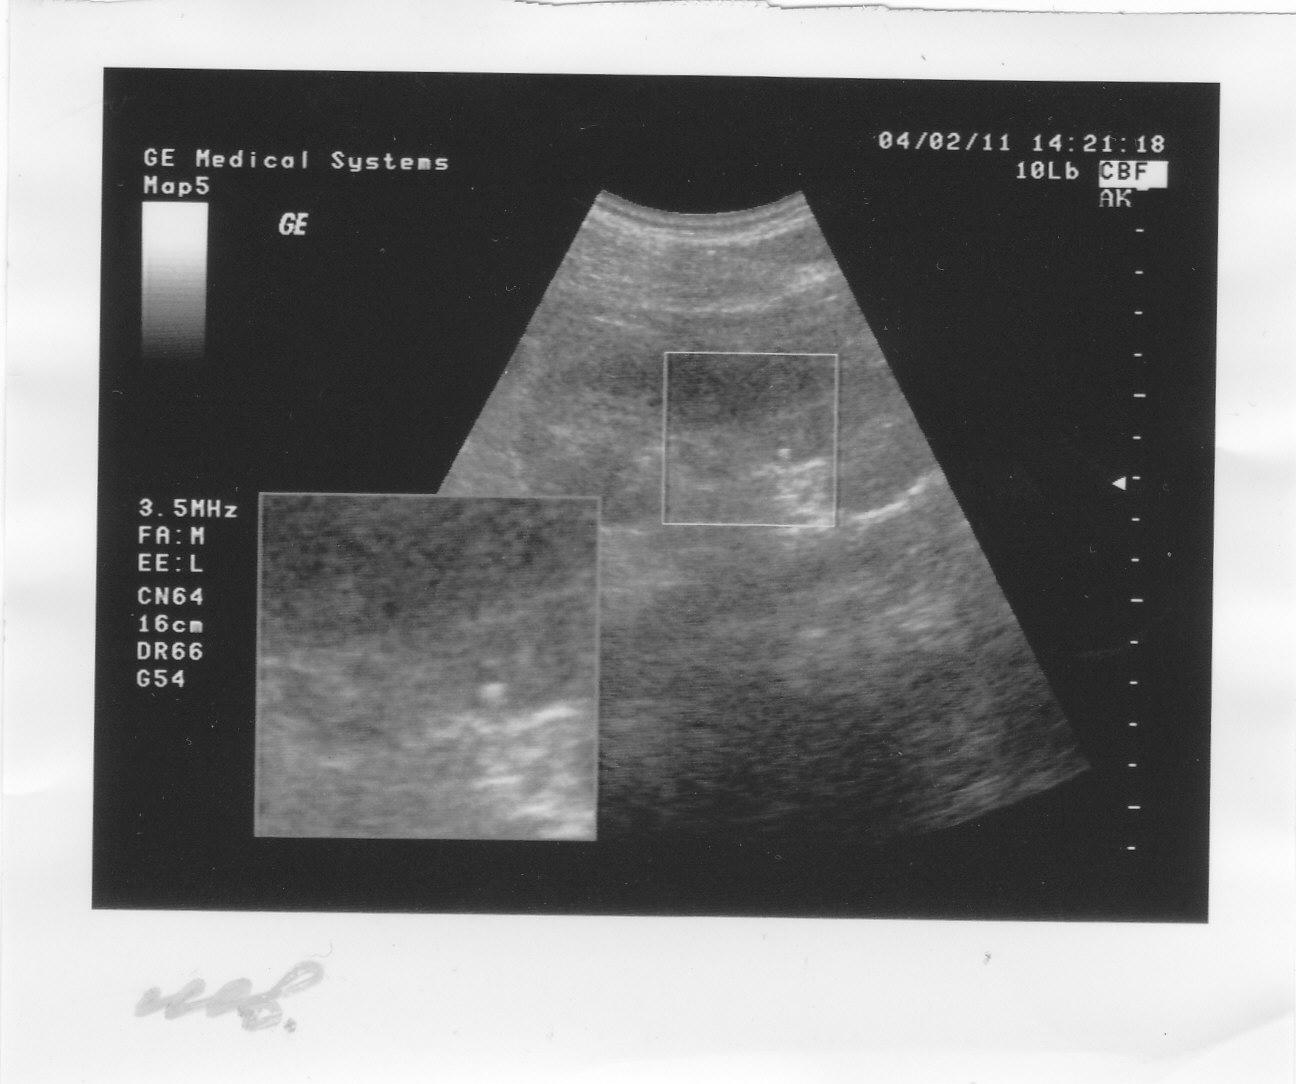

это камни или соли на снимке УЗИ

А в 2010 году на снимке видно что то в правой, не оперированой почке.Анализы все в норме.

В 2011 году сделаны снимки обеих почек на консультацию к урологу.Анализы все в норме.

Отправляю снимки УЗИ.